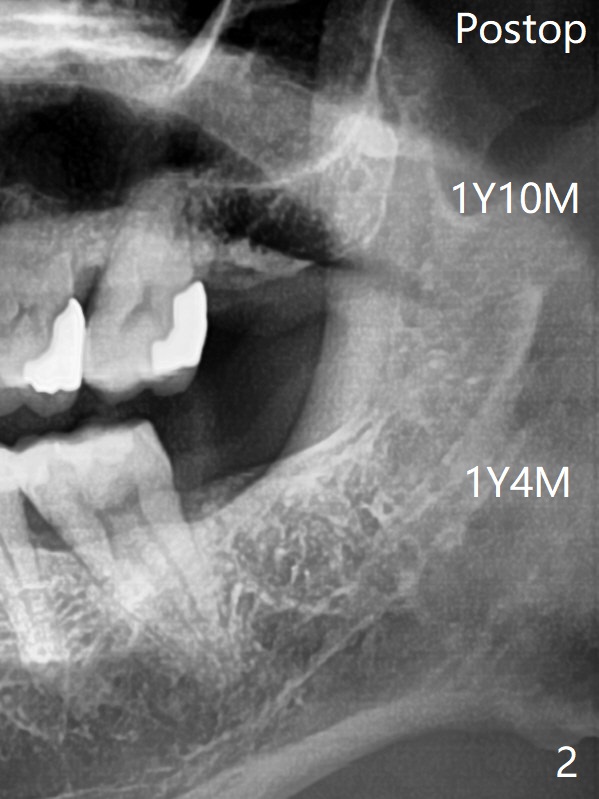

Xin Wei, DDS, PhD, MS 1st edition

10/16/

2020, last revision 10/17/2020